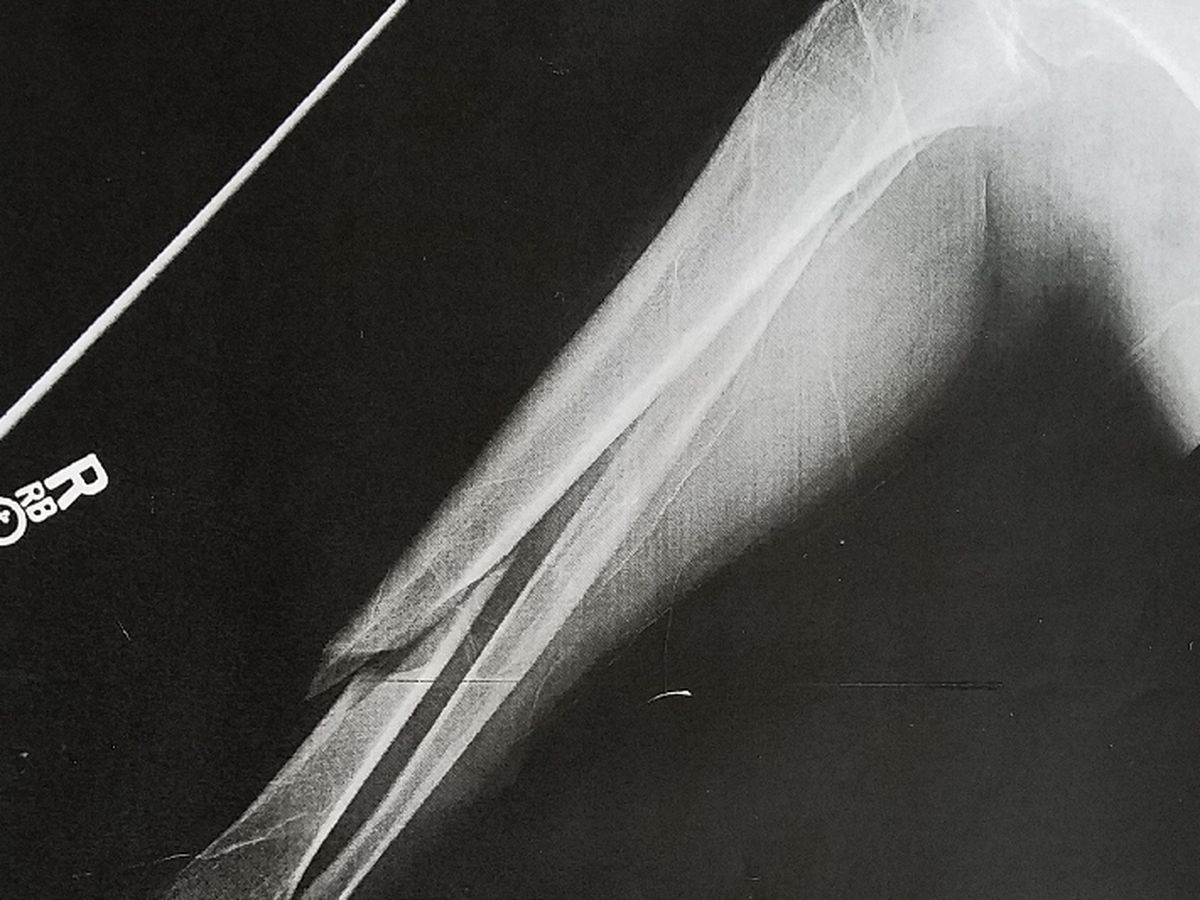

I'm 30 days into 90+ days of recovery for a displaced broken tibia bone and fibula bone. (90 days non-weight bearing and then physical therapy).

Reality has set in after 4 weeks that this is not going to be an easy recovery. As you can see from the photos it was a bad break. After 4 weeks my ankle and foot still swells up and turns black if I'm not flat on my back with my leg elevated above my heart. Because of this I'm very limited on how much work I can do on my computer, and of course I can't do any type of on site work at this time.